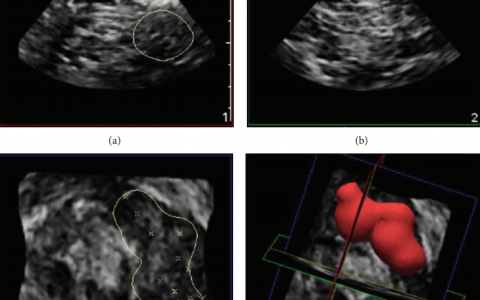

• 四维超声在神经阻滞中的应用

亲爱的小花帽们,你们还在纠结二维超声引导下神经阻滞技术无法突破么?你还在准备学习或掌握三维引导下神经组织么?而四维超声引导下神经阻滞已经来袭。N. J. Clendenen等制订了一个四维超声引导下神经阻滞的方法。…